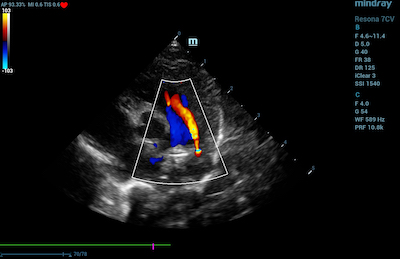

- Heart – Echocardiography utilizes a type of CDI that examines the heart and the velocity of blood flow through the cardiac valves and detects any irregularities between the left and right sides of the heart. CDI of the heart can also determine if there is any blood leakage through the valves.

Color Doppler Imaging of Patent Ductus Arteriosus